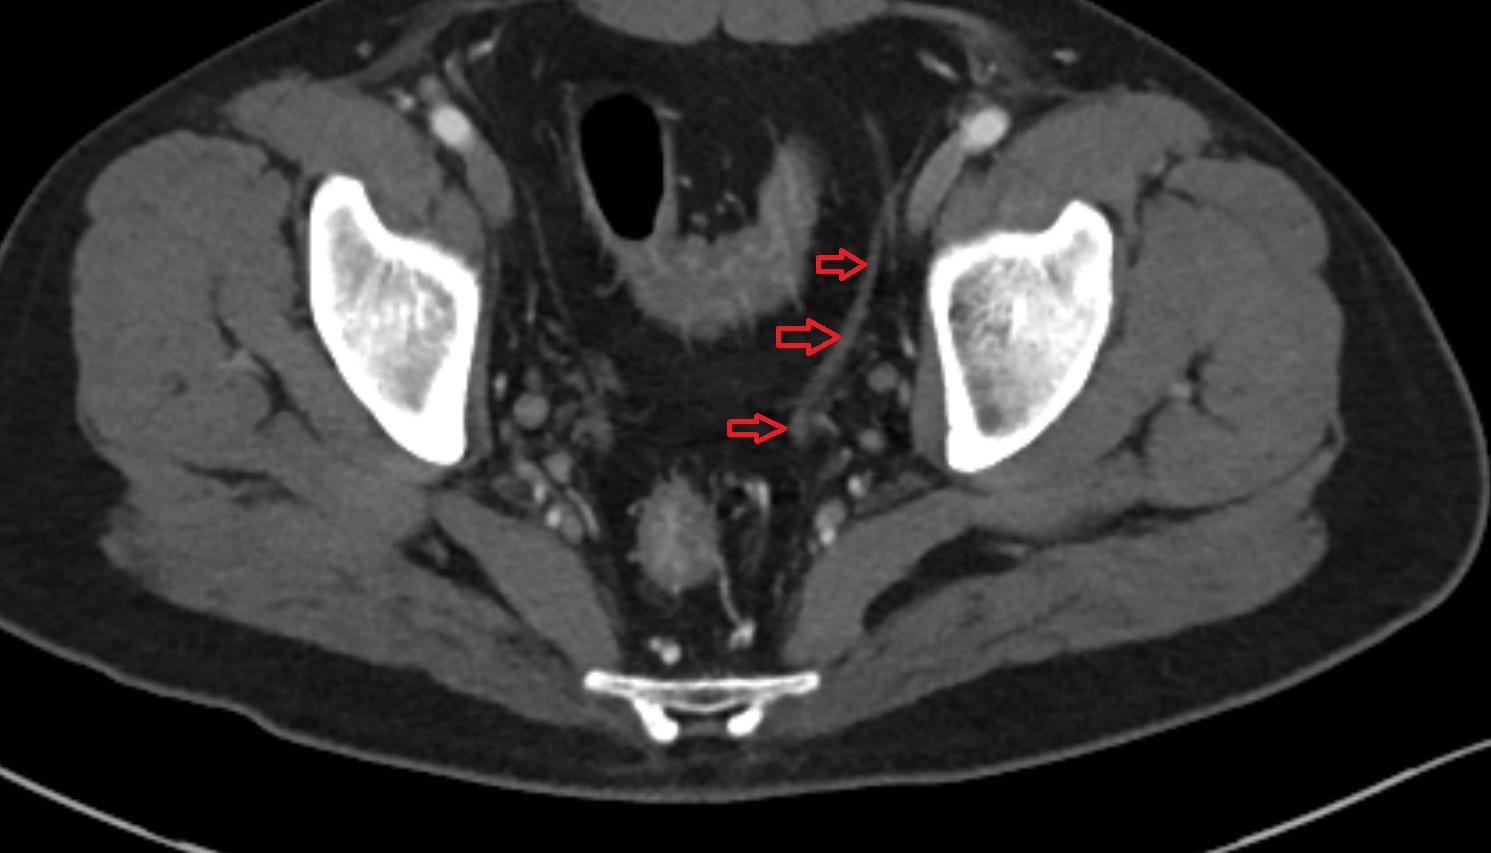

- Inguinal lymph nodes

- Intermediate lacunar external iliac lymph nodes

- External iliac lymph nodes

- Obturator lymph nodes